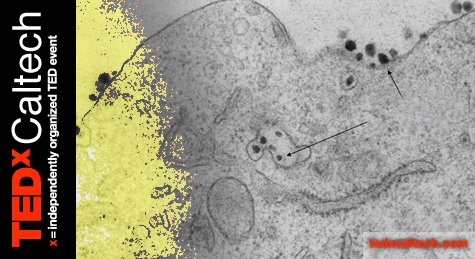

Mark Davis, a chemical engineer at Caltech, will discuss his efforts to design nanoparticles to battle cancer. After seeing his wife suffer through aggressive chemotherapy in 1995, Davis set out to find a cancer treatment that would avoid the harmful side effects that are often as damaging as the disease itself. Over the last 15 years, Davis and his colleagues have designed nanoparticles—tiny spheres about 30 to 70 nanometers in diameter—that target tumors and deliver cancer-killing agents. Unlike the materials used in traditional therapies that involve tiny molecules, these nanoparticles are too big to penetrate other body tissues, thereby avoiding many harmful side effects. At the same time, they're just the right size to find their way to cancer cells.

Recently, Davis and his colleagues have packed double-stranded RNA, a molecule similar to DNA, into nanoparticles. Through a process called RNA interference, for which the 2006 Nobel Prize in Physiology or Medicine was awarded, the double-stranded RNA is able to silence particular genes and prevent them from functioning. By silencing the specific genes responsible for particular cancers, this technique would be a powerful way to combat cancer at the genetic level—a method that avoids the complications and potential side effects of therapies that focus on individual proteins.

The researchers engineered the nanoparticles so that after the particles make their deliveries, they fall apart and leave the body via urine. In the last year, Davis and his team have shown, for the first time, that this technique works in cancer patients. "It's a clear example of nanotechnology enabling new biotechnology for therapeutic use in humans," Davis says. He envisions that cancer treatment in the future will be not only personalized but dynamic. If the cancer mutates, doctors can simply change the genetic target of the nanoparticles accordingly.